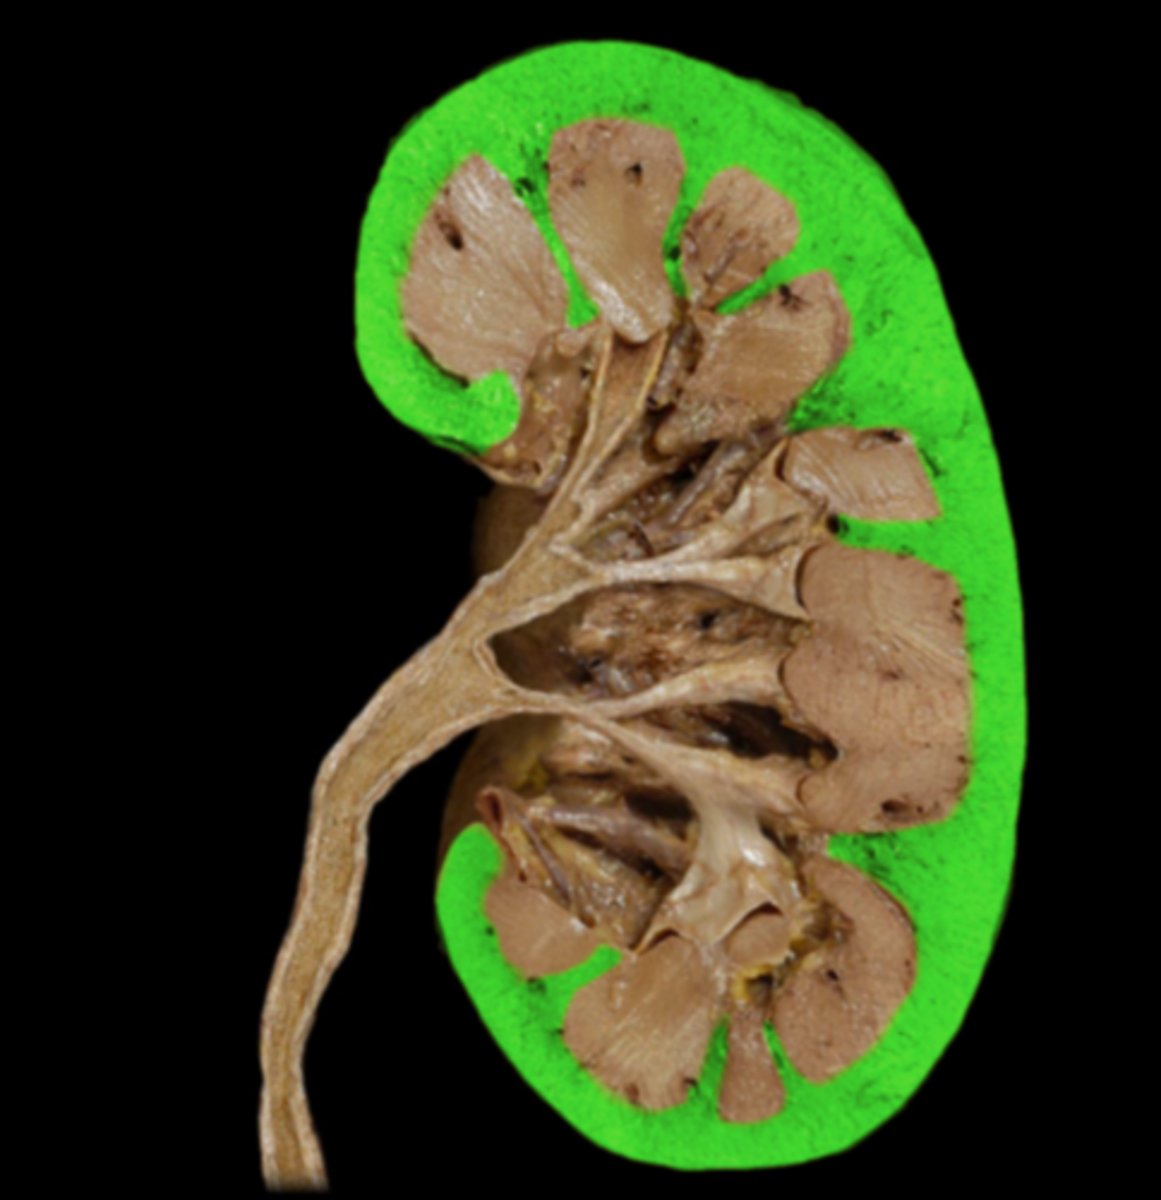

Renal Capsule

Renal Cortex

Renal Medulla

Papilla

Renal Column

Minor Calyx

Major Calyx

Renal Pelvis

Renal Hilum